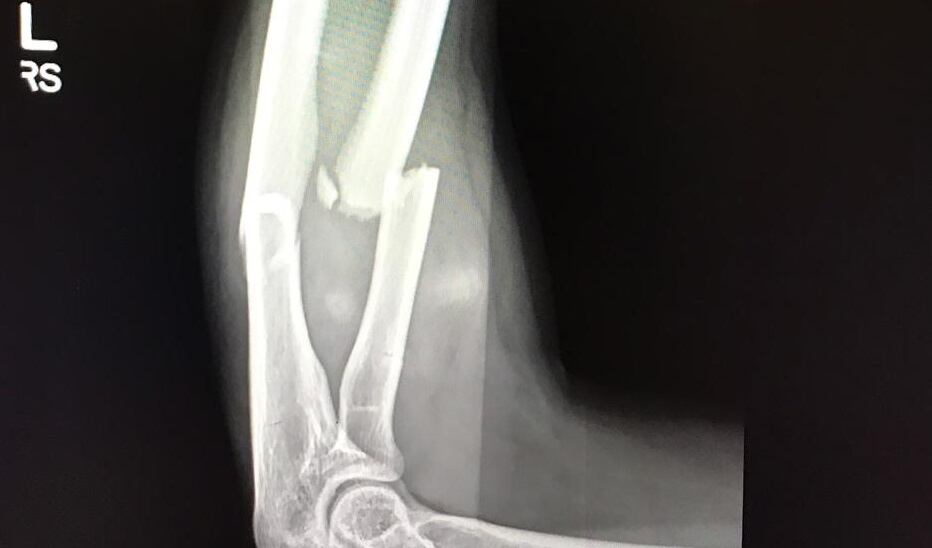

La guardameta de 24 años se quebró el antebrazo (fractura de radio y cúbito) el 5 de octubre, durante el Premundial femenino. Los gritos de dolor dejaron en evidencia que se trataba de algo grave.

Dos placas y 14 pines son su mayor recuerdo de la primera operación a la que se ha tenido que someter en su carrera.